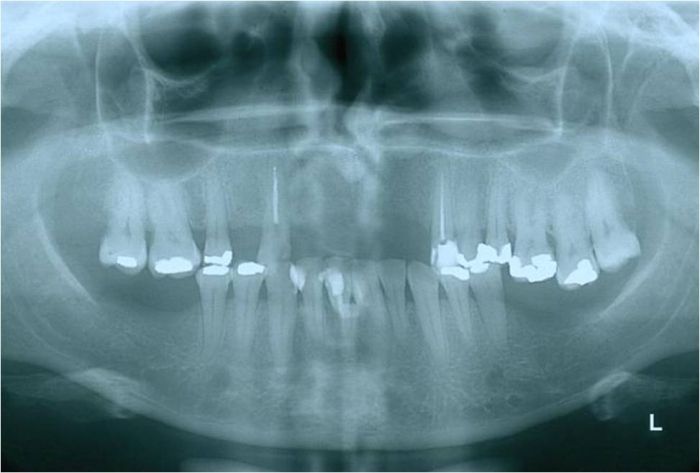

Raio x após enxerto ósseo e implantes

Raio x com próteses provisórias sobre implantes cone morse

Raio x final